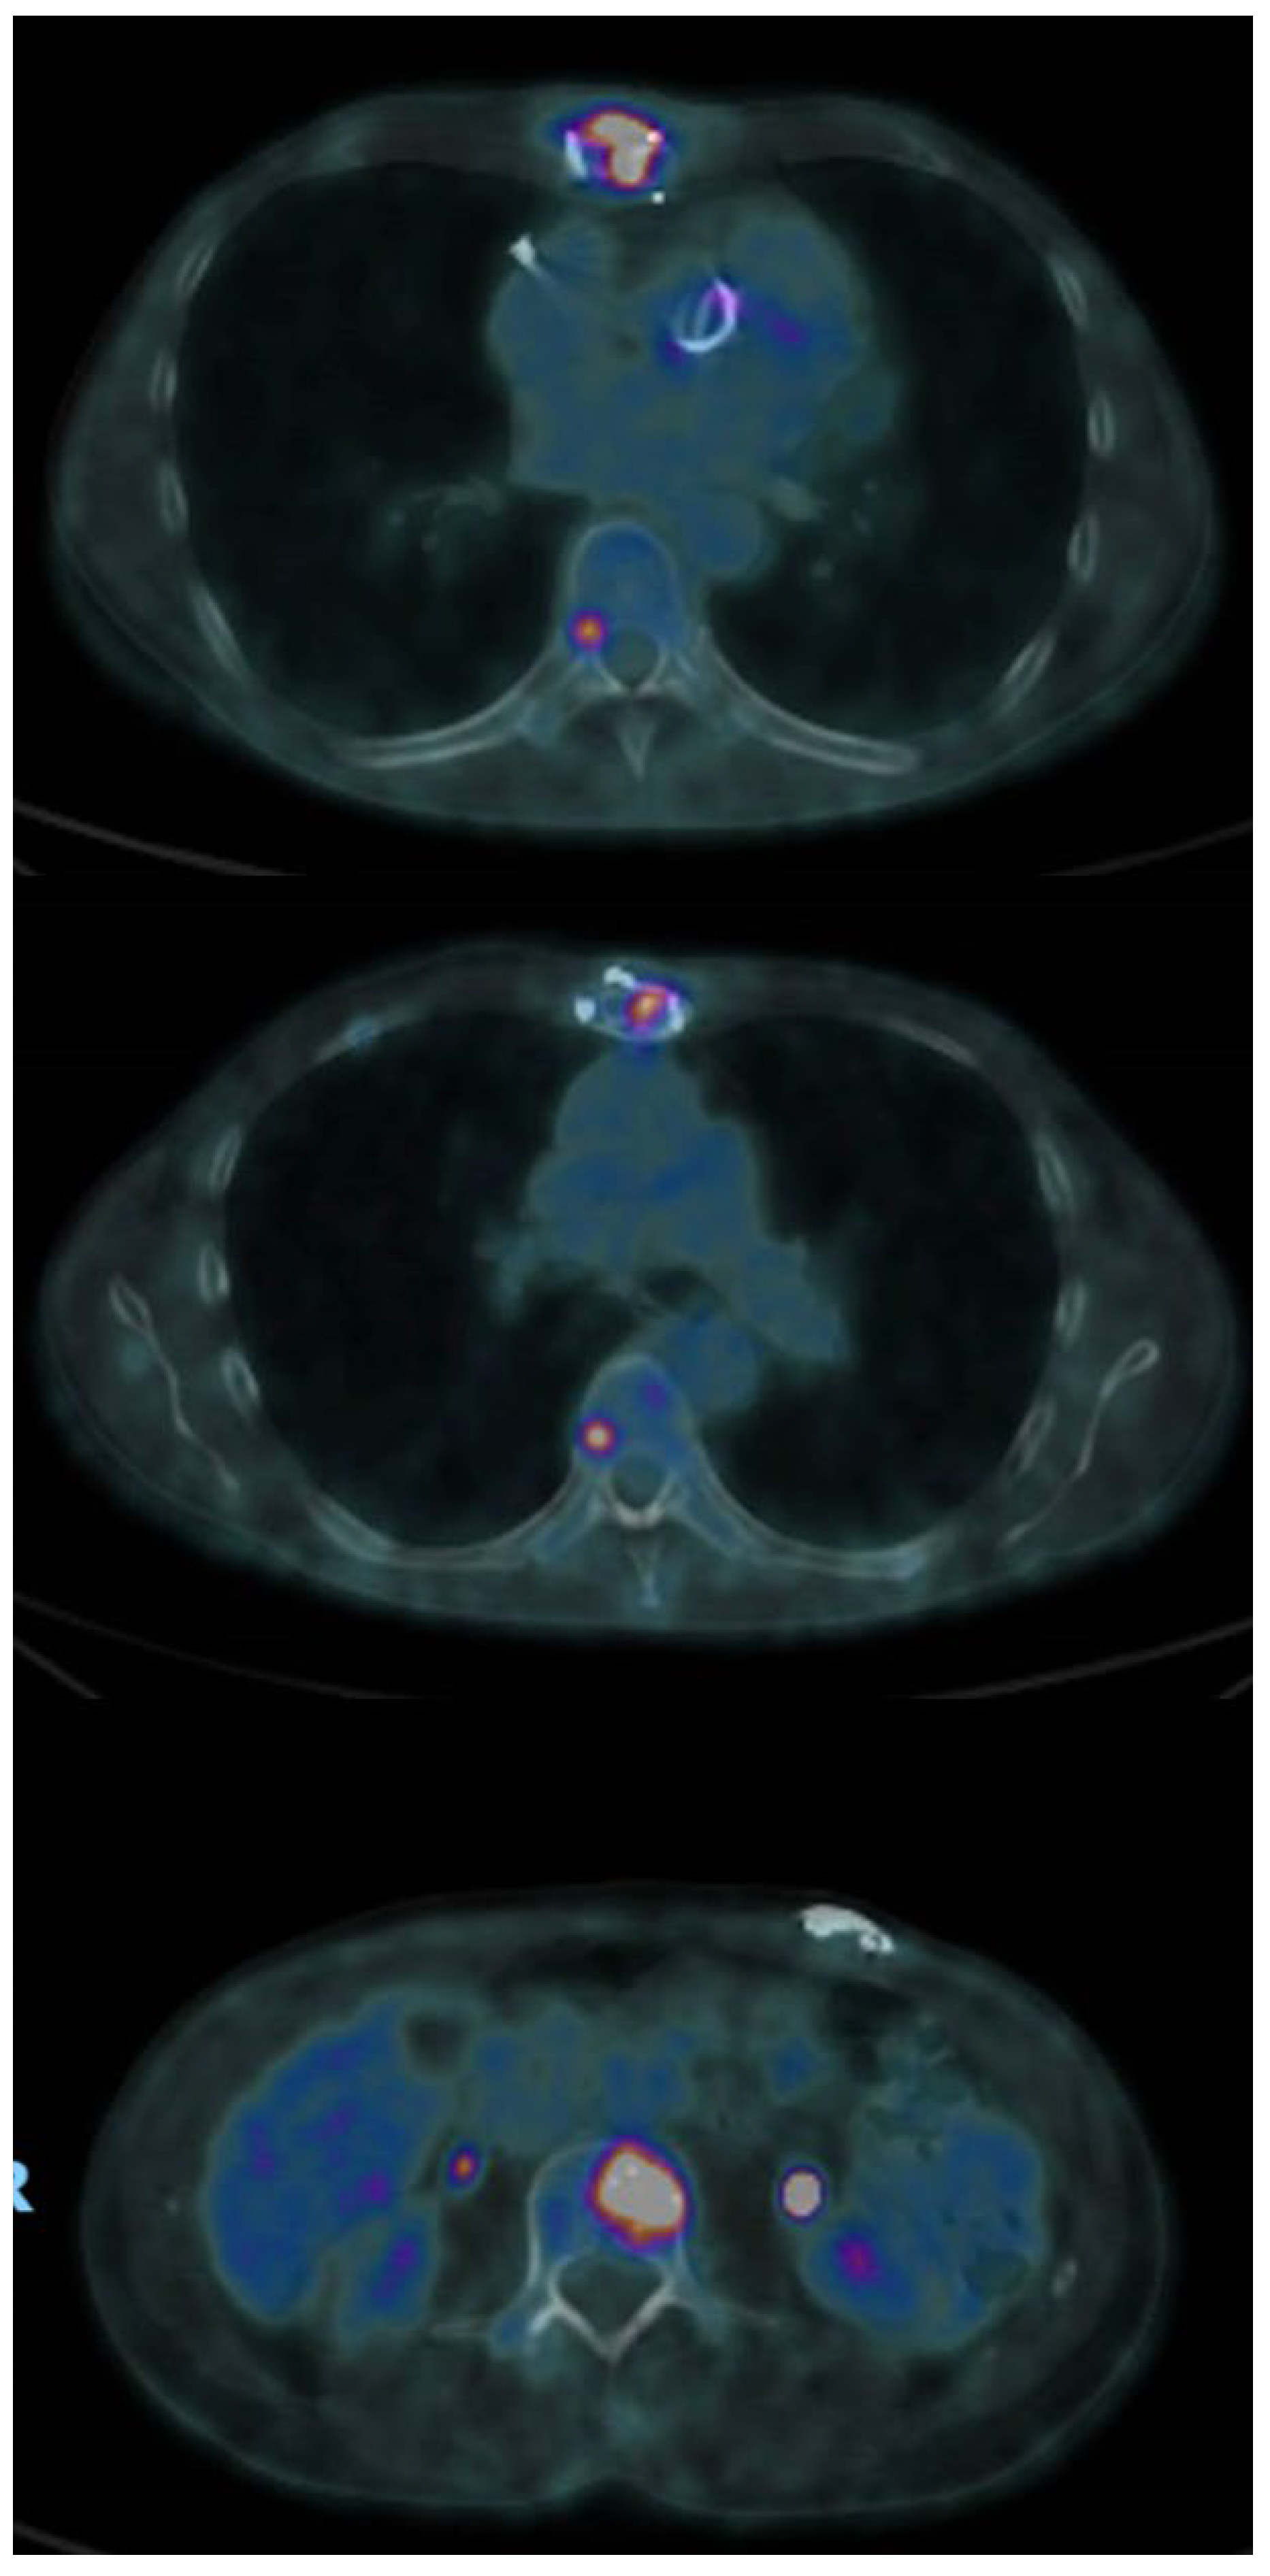

- Bleeker-Rovers, C.P.; Vos, F.J.; A Wanten, G.J.; Van Der Meer, J.W.M.; Corstens, F.H.M.; Kullberg, B.-J.; Oyen, W.J.G. 18F-FDG PET in detecting metastatic infectious disease. J. Nucl. Med. Off. Publ. Soc. Nucl. Med. 2005, 46, 2014–2019. [Google Scholar]

- Zhang, R.; Feng, Z.; Zhang, Y.; Tan, H.; Wang, J.; Qi, F. Diagnostic value of fluorine-18 deoxyglucose positron emission tomography/computed tomography in deep sternal wound infection. J. Plast. Reconstr. Aesthet. Surg. 2018, 71, 1768–1776. [Google Scholar] [CrossRef] [PubMed]

- Elsheikh, A.; Elazazy, M.; Elkaramany, M. Role of 18F-FDG PET-CT in Pre-Operative Planning of Surgical Debridement in Chronic Osteomyelitis. Indian J. Orthop. 2022, 56, 2237–2244. [Google Scholar] [CrossRef] [PubMed]